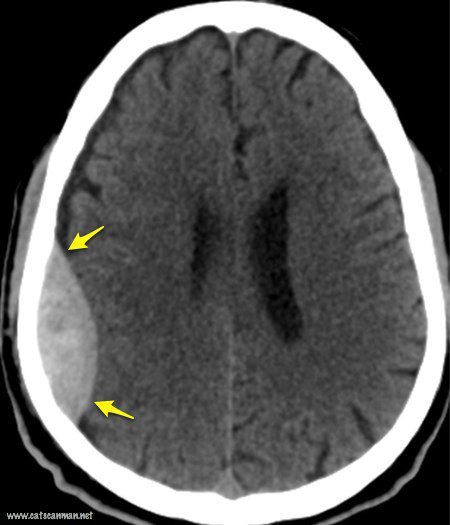

(Total Questions - 15)Q.1. Read the CT report

Correct Answer : B